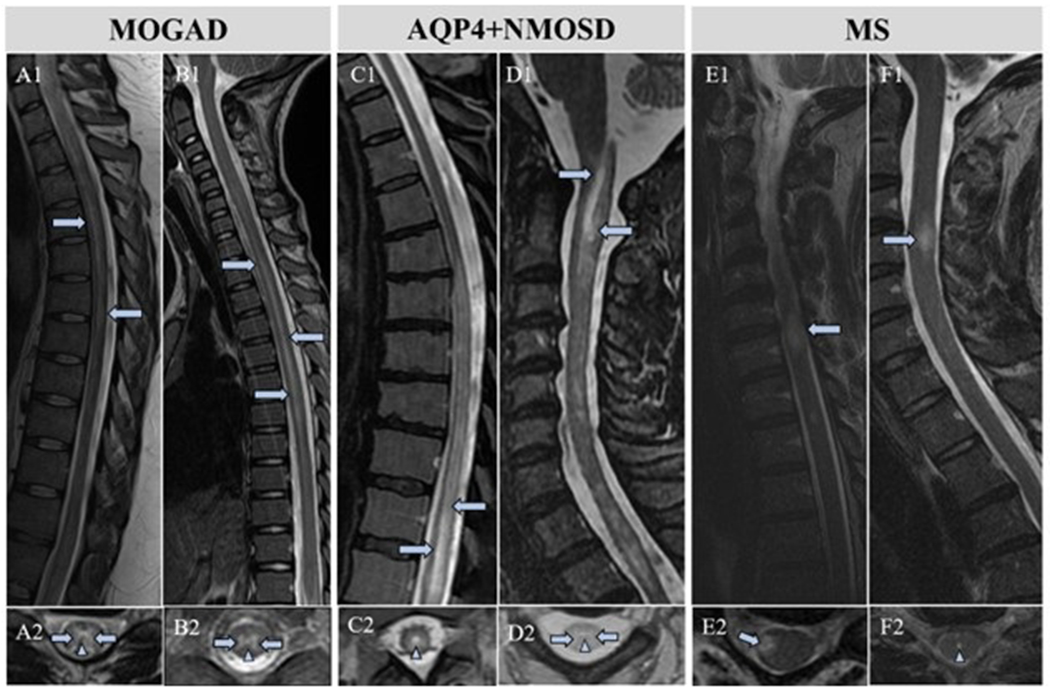

We included 126 patients with acute myelitis (MOGAD n=63, AQP4+NMOSD n=37, and MS n=26). Marked central canal T2-hyperintensity was observed frequently in MOGAD (Figure 1) and AQP4+NMOSD (Figure 2) but was very rare in MS (Table 1). There was no difference in the frequency of marked central canal T2-hyperintensity on axial imaging in MOGAD (18/63[29%]) versus AQP4+NMOSD (13/37[35%]; p=0.49). A corresponding central canal T1-hypointensity was more frequent in patients with AQP4+NMOSD myelitis (6/13[46%]) compared to MOGAD (2/18[11%]; p=0.04). The single MS myelitis patient with marked central canal T2-hyperintensity did not have a corresponding T1-hypointensity. Most cases of marked central canal T2-hyperintensity resolved on follow-up axial MRI for MOGAD patients (12/14[86%]; Figure 1C) and AQP4+NMOSD patients (10/10[100%]; p=0.49).

Figure 2.

MRI comparison of marked central canal T2-hyperintensity in MOGAD, AQP4+NMOSD, and MS myelitis. MOGAD patients with characteristic linear T2-hyperintensities on sagittal MRI (A1, B1, arrows) with marked central canal T2-hyperintensity (A2, B2, arrowheads). Longitudinally extensive T2-hyperintense signal changes in AQP4+NMOSD patients (C1, D1, arrows) with marked central canal T2-hyperintensities (C2, D2, arrowheads). Classic MS lesion (E1, arrow) without marked central canal T2-hyperintensity (E2, arrow). MS patient in our study with a typical demyelinating spinal cord lesion (F1) and the only MS patient with a marked central canal T2-hyperintensity (F2, arrowhead).